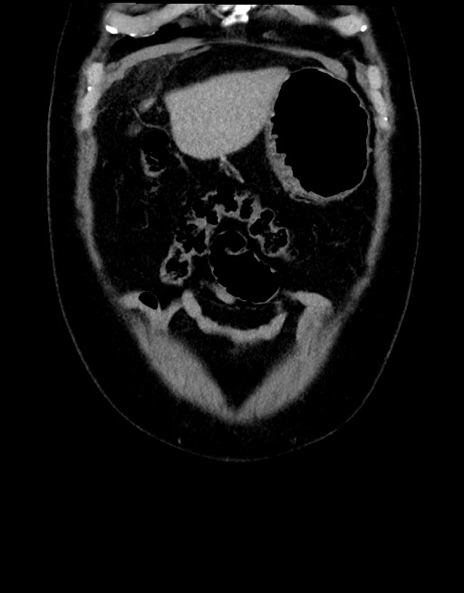

症例15(冠状断像)

【症例】70歳代男性

【主訴】腹痛

【現病歴】今朝から腹痛あり。全体的に痛い。特に左上の方。排ガスが今日はない。冷や汗が出る。

【既往歴】直腸癌術後

【身体所見】左側腹部〜上腹部に圧痛あり。腹膜刺激症状明らかなではない。軽度反跳痛。左下腹部に術後瘢痕あり。

【データ】WBC 7700、CRP 0.02

横断像